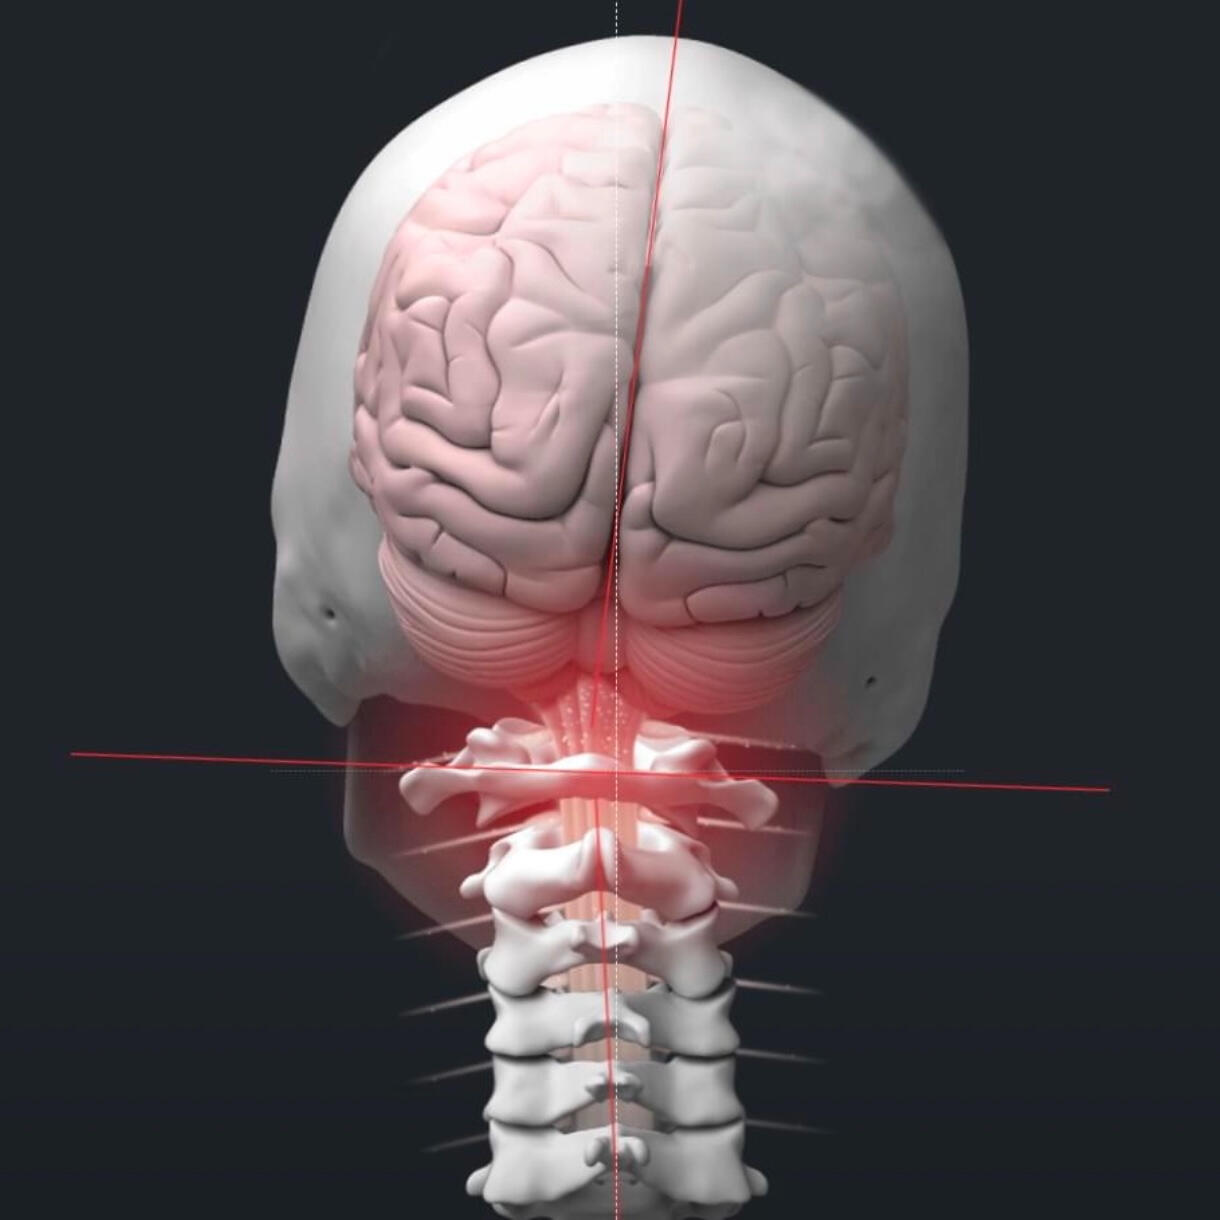

Our chiropractic care focuses on how the brain and nervous system communicate with the body. We use precise, specific adjustments, not force, to support function and healthy adaptation.This approach is gentle and safe for families, children, and athletes alike. The goal is not chasing symptoms, but helping the body change how it adapts and functions over time.

Spinal disc injuries require more than symptom-based care. Our spinal disc rehabilitation approach in Inver Grove Heights focuses on restoring movement, reducing pressure on the disc, and improving how the spine and nervous system work together over time. Care is guided by imaging, clinical findings, and measured progress, not guesswork or force.This care is designed for people dealing with disc herniations, disc bulges, sciatica, chronic back or neck pain, and those who have not improved with traditional chiropractic care. It is also appropriate for individuals looking for non surgical disc care before considering injections or surgery.